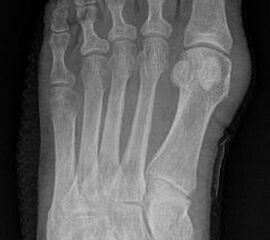

Abb. 3a, b: Präoperatives (a) und postoperatives (b) Röntgenbild bei Korrektur einer Typ I Deformität durch eine Exostosenabtragung.